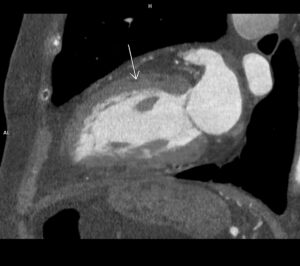

Discuţie caz nr 96: Boală Barlow este un sindrom clinic datorat prolapsului de valvă mitrală; se evidențiază deplasarea în sistolă a cuspelor mitrale spre atriul stâng ce asociază disjuncţie de inel mitral și fenomen de curbare posterioară. Această forțare a miocardului ventricular stâng din segmentele laterale poate duce la apariția de arii de fibroză că substrat aritmogen – materializate sub formă de priză de contrast (nu e cazul la acest pacient).